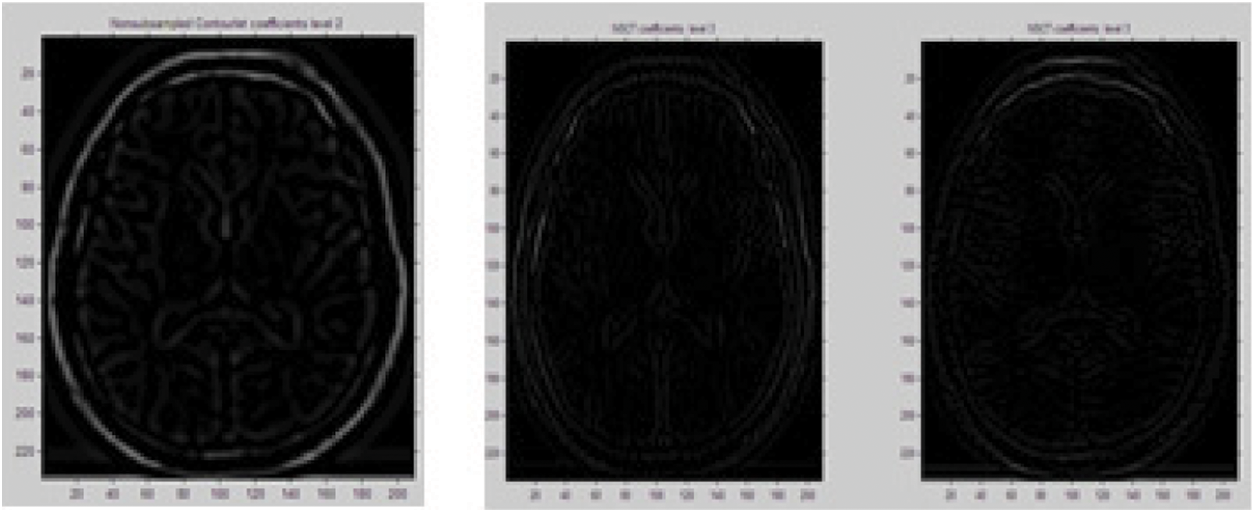

The perform experimental analysis of the proposed system, two different types of medical image mentioning CT image and MRI of different modality were considered. The image group C and M are to be fused. On simulating our algorithm, we implement three levels of decomposition of input images by the proposed NSCT. To analyze the performance of the proposed method we implement Discrete Cosine transformation and Discrete Wavelet transformation method and the results were depicted in Fig. 9. The Fig. 9 portrays the fused results of two different modality image mentioning Computer Tomography Image and Magnetic Resonance Image.

Figure 9: NSCT coefficients extracted from source image

The Fig. 9 depicts the process of extracting the NSCT first level of coefficient from the multimodal source image, through which the successive levels of NSCT coefficients were extracted which, is depicted in Fig. 10.

Figure 10: NSCT coefficient 2 and 3 extracted from coefficient 1